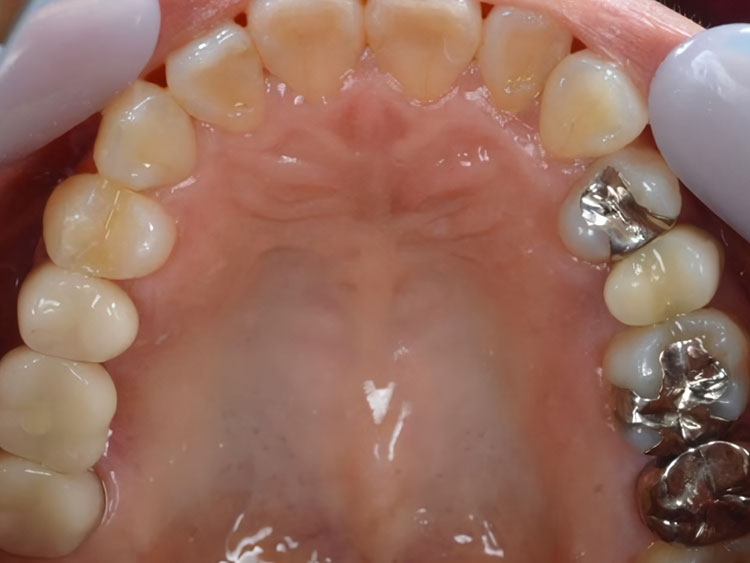

インプラント症例 Case3

Treatment cases

Before

After